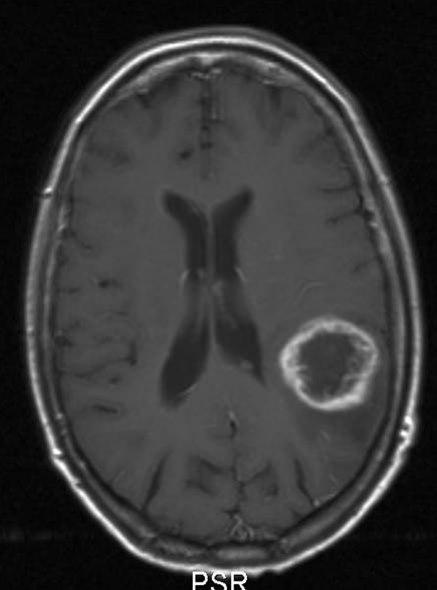

Glioblastom, aksialt snitt

glioblastom who grad iv 2

Glioblastom WHO grad IV

Gjengitt med tillatelse av Radiologisk avdeling, Universitetssykehuset Nord-Norge